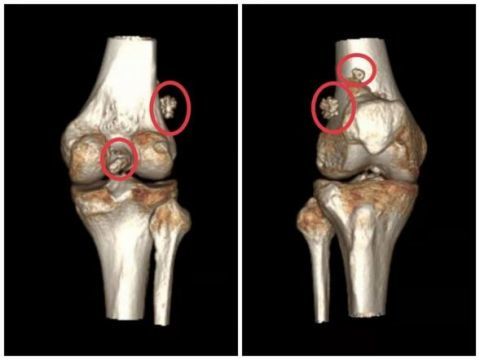

在当地医院做了x线检查, 当地医生发现 王师傅的膝关节里密密麻麻的